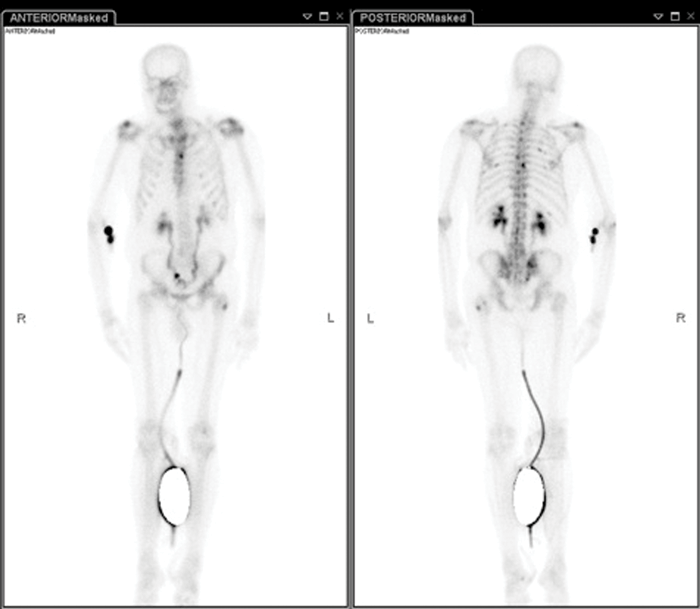

1. What abnormalities are seen on this bone scan?

2. What is the mostly likely urological diagnosis?

3. What is the radiation dose of this scan?

Case 3

Increased uptake in thoracic spine, pelvis and left femur suggestive of bony metastases. Bilateral hydronephrotic kidneys. Patient is catheterised. Extravasation at injection site in right antecubital fossa.

-

Bony metastases secondary to prostate cancer, with bilateral hydronephrosis secondary to bladder invasion or pelvic lymphadenopathy.

6.3mSv.